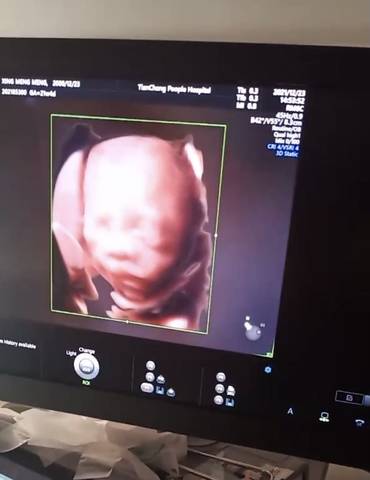

你们能看得出男女?你们觉得是男孩女孩

journal_insert_pic_1685508796

你好,根据你发的检查报告,是看不出宝宝的性别的,建议宝妈还是安心养胎,只要宝宝健康就好

你好亲爱的,通过这个来判断男孩女孩是不太准确的哈,我们要给他同等的关爱和呵护,也祝你可以如愿以偿,心想事成。

你好。我们是判断不了男宝宝跟女宝宝的,孕期定期检查,我觉得宝宝健康就好的。祝心想事成 。